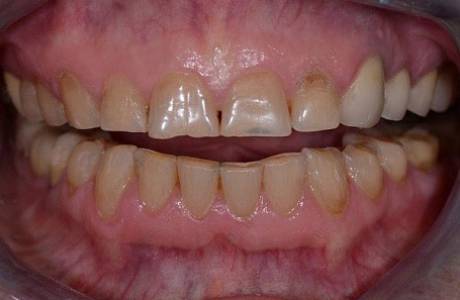

До лечения

Пациент обратился с жалобой на разрушение зубов.

После лечения

На верхней челюсти было принято решение установить E-max коронки.На нижней челюсти E-max виниры. Пациент полностью доволен свой новой красивой улыбкой.